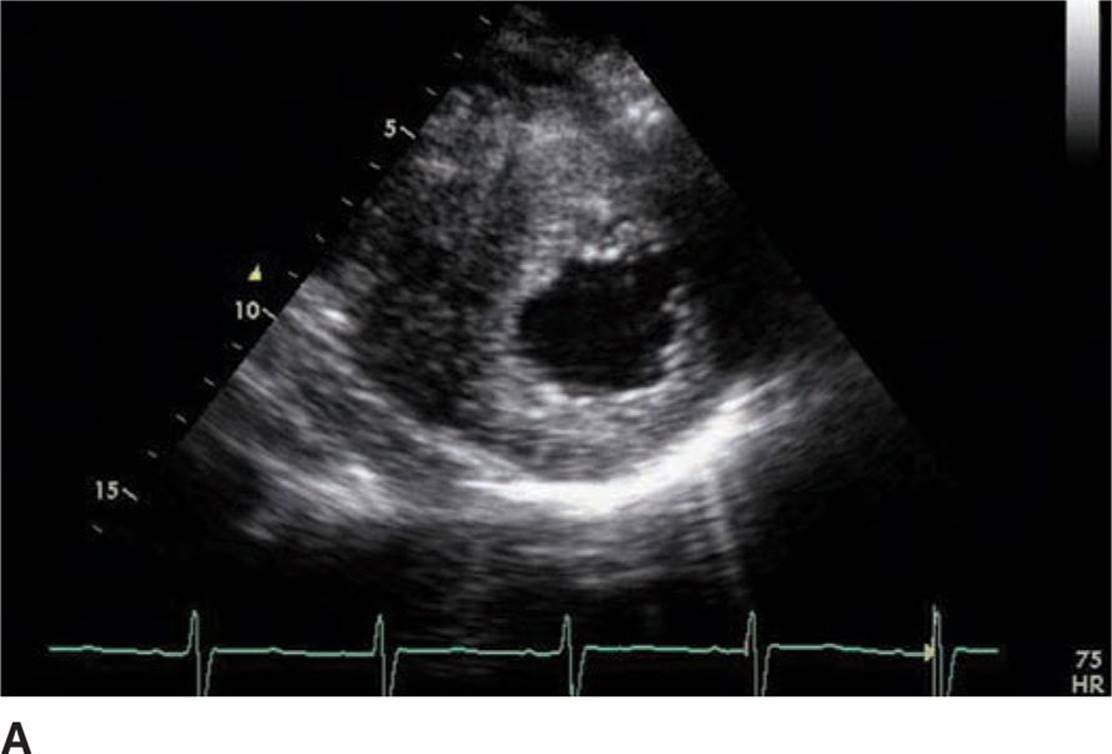

FIGURE 53-3A Parasternal short axis view of left ventricle in diastole.

FIGURE 53-3B Parasternal short axis view of the left ventricle in systole.